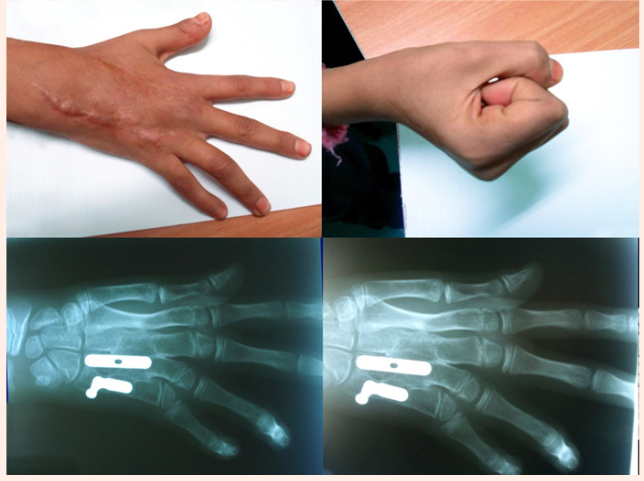

On clinical examination she presented with an obvious functional and cosmetic impairment of the hand, with disability on grasping and also she was unable to make a strong grip because the fixed position of the ring and little finger and the inability of close them together (Figure 1A & 1B). Two old scars were clearly seen in the dorsum of her hand. The third web space was wider that the others web spaces. The ulnar two metacarpals were shorter and ulnarly angulated with not adduction/abduction motion between them. The physiological arch of the hand was lost as well as the normal position of the knuckles, but no rotation deformity was appreciated.

No neurovascular deficit were associated, The radiographies and CT scan revealed and confirmed an old healed fracture of the second metacarpal less than 20 degrees angulate radically, healed fractures producing complete post-traumatic fusion of the third, fourth and fifth metacarpal at mid shaft level (Figure 1C & 1D) with 30 degrees of ulnar, palmar angulation and associated shortening of the fourth and fifth metacarpals. After careful study of the CT scans (Figure 1D), a detailed surgical plan was decided with the idea of reproduce the previous fracture pattern, doing the corrective osteotomies at the level of the intra callus area. Under general anaesthesia and tourniquet application, a single incision was done across the dorsum of the hand between the fourth and fifth metacarpal, the post-traumatic metacarpal synostosis area was exposed after a careful separation of the extensor tendons.

Figure 1A Shows hand deformity. Two old scars appear in the dorsum of the hand.

Figure 1B Third space is wider with not adduction/abduction between the 3rd and 4th. Unable to make a strong grip.

Figure 1C Radiography, oblique view.

Figure 1D CT scan reveals an old healed fracture of the second metacarpal less than 20 degrees angulated radially, complete post-traumatic fusion of the third, fourth and fifth metacarpal at mid shaft level.